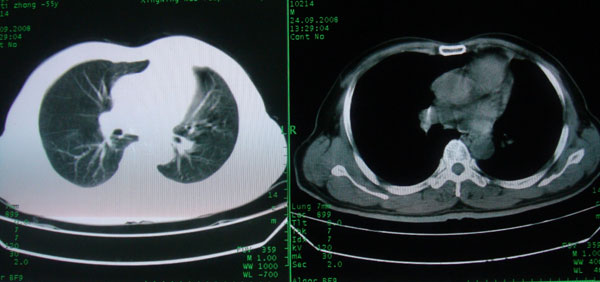

患者男性58岁因二周前起咳嗽,今天胸片示左上肺占位性病变行ct检查,无发热,无咯血痰.

左肺上叶病灶,实变但见含气支气管、空洞但未见壁内结节及积液;

考虑:①感染性病变(包括特殊感染型肺tb)

②肿瘤性病变(考虑患者年龄比较大的关系/所以不排除)

初学者。。。左肺空洞性病变,并可见阻塞性肺不张改变,鉴于患者为老年男性,且临床症状仅有咳嗽,全身中毒症状不明显,所以我首先考虑为左肺癌性空洞并左侧肺门淋巴结转移伴左肺阻塞性肺不张。结核性空洞放于第二位考虑,可以进行相关实验室检查。希望能有病理结果,谢谢!!!!!

左肺上叶实变影,内见支气管充气征及空洞影,病人年龄较大,无发热及结核中毒症状,心影左移,未见纵隔淋巴结肿大;不知实验室检查结果如何?有否嗜酸细胞增多,有没有进行治疗?就目前资料首先考虑1.感染性病变,2.慢性嗜酸性肺炎?可结合实验室检查并短期治疗复查,肺癌不能排除。